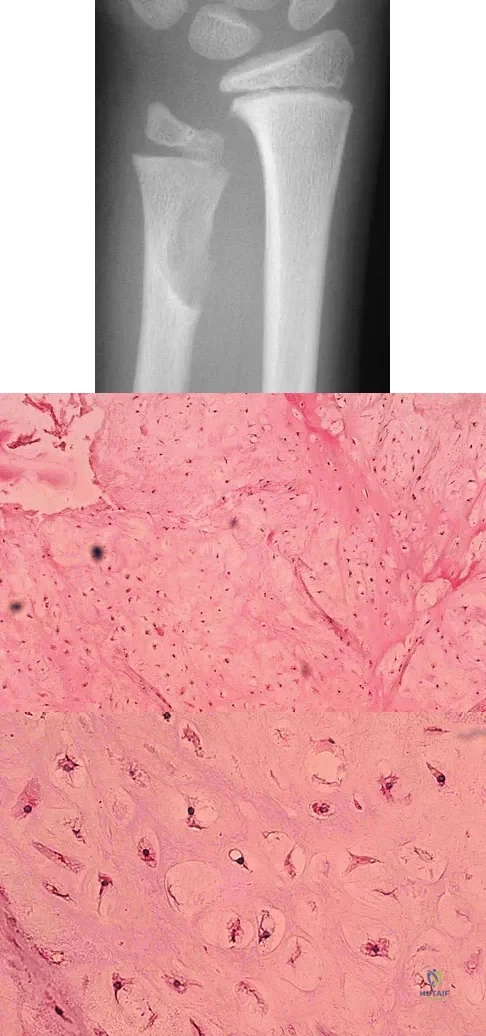

A 10-year-old boy has had wrist pain for the past 3 months. He denies any history of trauma. He reports mild tenderness associated with a palpable mass. A radiograph and biopsy specimens are shown in Figures 52a through 52c. What is the most likely diagnosis?

An otherwise healthy 75-year-old man has a painful mass in the popliteal fossa of his right knee. A lateral radiograph of the knee, a CT scan of the distal femur, and a histopathologic specimen are shown in Figures 13a through 13c. Management should consist of